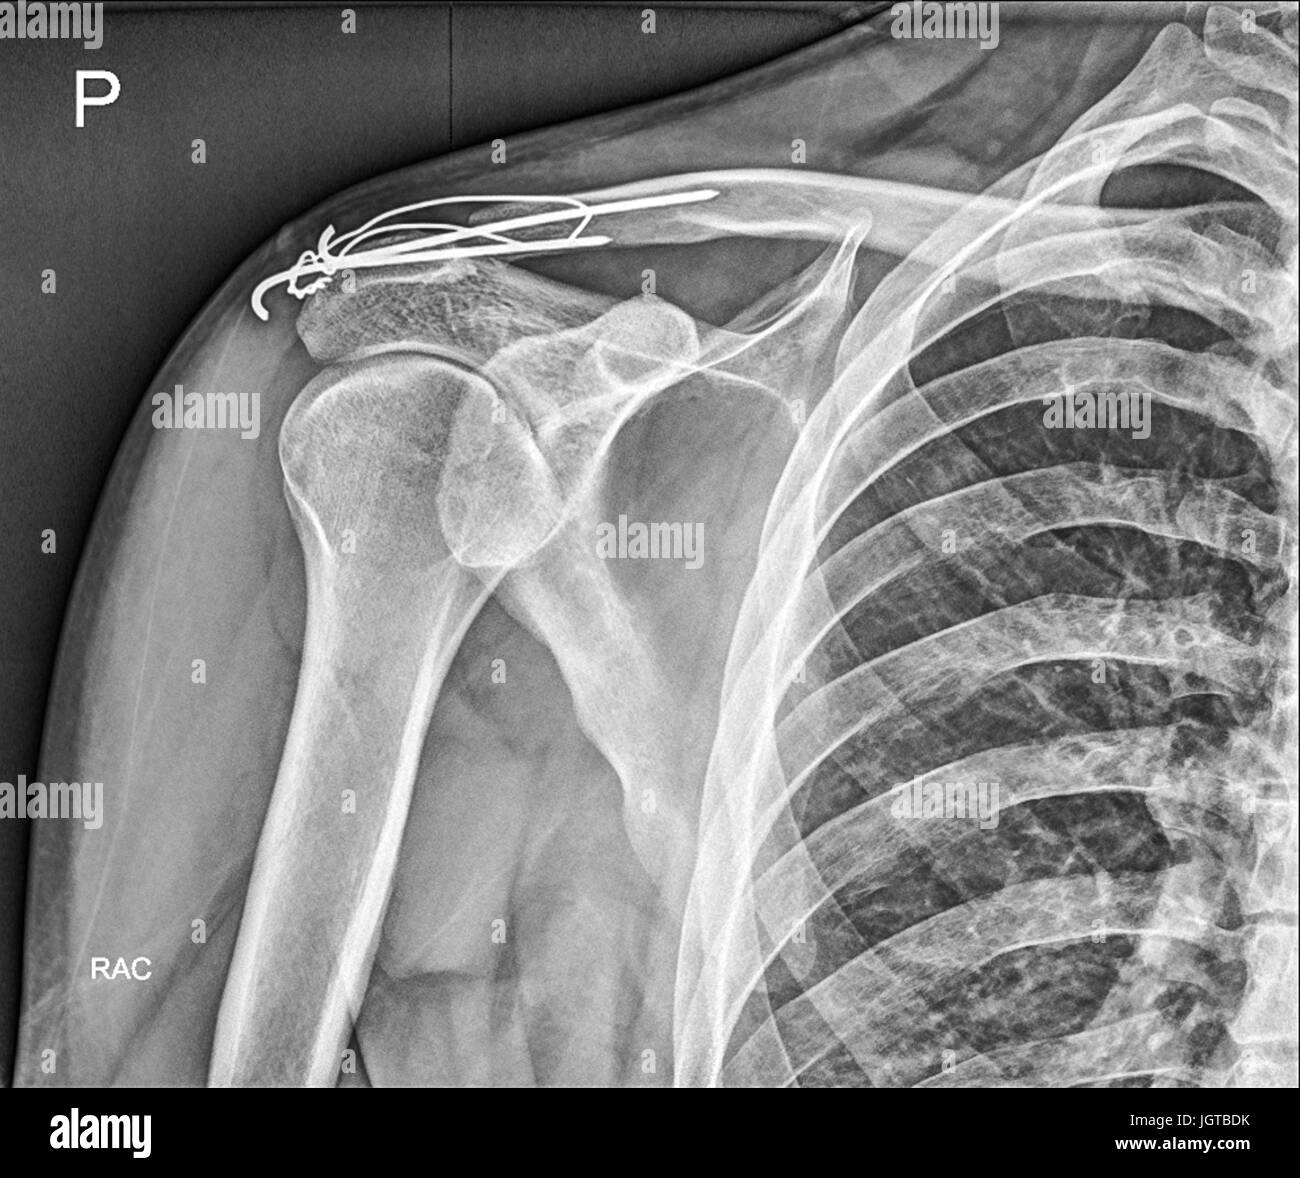

Ache Under Clavicle. If you experience these symptoms, go straight to the emergency room: A ruptured spleen is a medical emergency. This pain can be caused by various factors, ranging from minor injuries to underlying medical conditions. Symptoms of a clavicle fracture is a pain in your upper chest and shoulder area, especially when you’re moving around. How would i treat a fracture? There also can be an obvious deformity in the shoulder, if severe. collarbone pain can be caused by a fracture, arthritis, a bone infection, or another condition related to the position of your clavicle. collarbone pain, also known as clavicle pain, can be a discomforting sensation experienced in the bone that connects the shoulder to the chest. You have two collarbones—one on each side of the front of your chest—that. why your collarbone is sore. Other symptoms include swelling, bruising, tenderness in the shoulder or collarbone area, and dizziness. it may feel like an ache in the spot where the top of the shoulder meets the end of the collarbone.

Other symptoms include swelling, bruising, tenderness in the shoulder or collarbone area, and dizziness. This pain can be caused by various factors, ranging from minor injuries to underlying medical conditions. If you experience these symptoms, go straight to the emergency room: A ruptured spleen is a medical emergency. collarbone pain can be caused by a fracture, arthritis, a bone infection, or another condition related to the position of your clavicle. it may feel like an ache in the spot where the top of the shoulder meets the end of the collarbone. How would i treat a fracture? You have two collarbones—one on each side of the front of your chest—that. Symptoms of a clavicle fracture is a pain in your upper chest and shoulder area, especially when you’re moving around. There also can be an obvious deformity in the shoulder, if severe.

Ache Under Clavicle This pain can be caused by various factors, ranging from minor injuries to underlying medical conditions. collarbone pain, also known as clavicle pain, can be a discomforting sensation experienced in the bone that connects the shoulder to the chest. This pain can be caused by various factors, ranging from minor injuries to underlying medical conditions. Other symptoms include swelling, bruising, tenderness in the shoulder or collarbone area, and dizziness. why your collarbone is sore. If you experience these symptoms, go straight to the emergency room: You have two collarbones—one on each side of the front of your chest—that. There also can be an obvious deformity in the shoulder, if severe. How would i treat a fracture? Symptoms of a clavicle fracture is a pain in your upper chest and shoulder area, especially when you’re moving around. A ruptured spleen is a medical emergency. it may feel like an ache in the spot where the top of the shoulder meets the end of the collarbone. collarbone pain can be caused by a fracture, arthritis, a bone infection, or another condition related to the position of your clavicle.